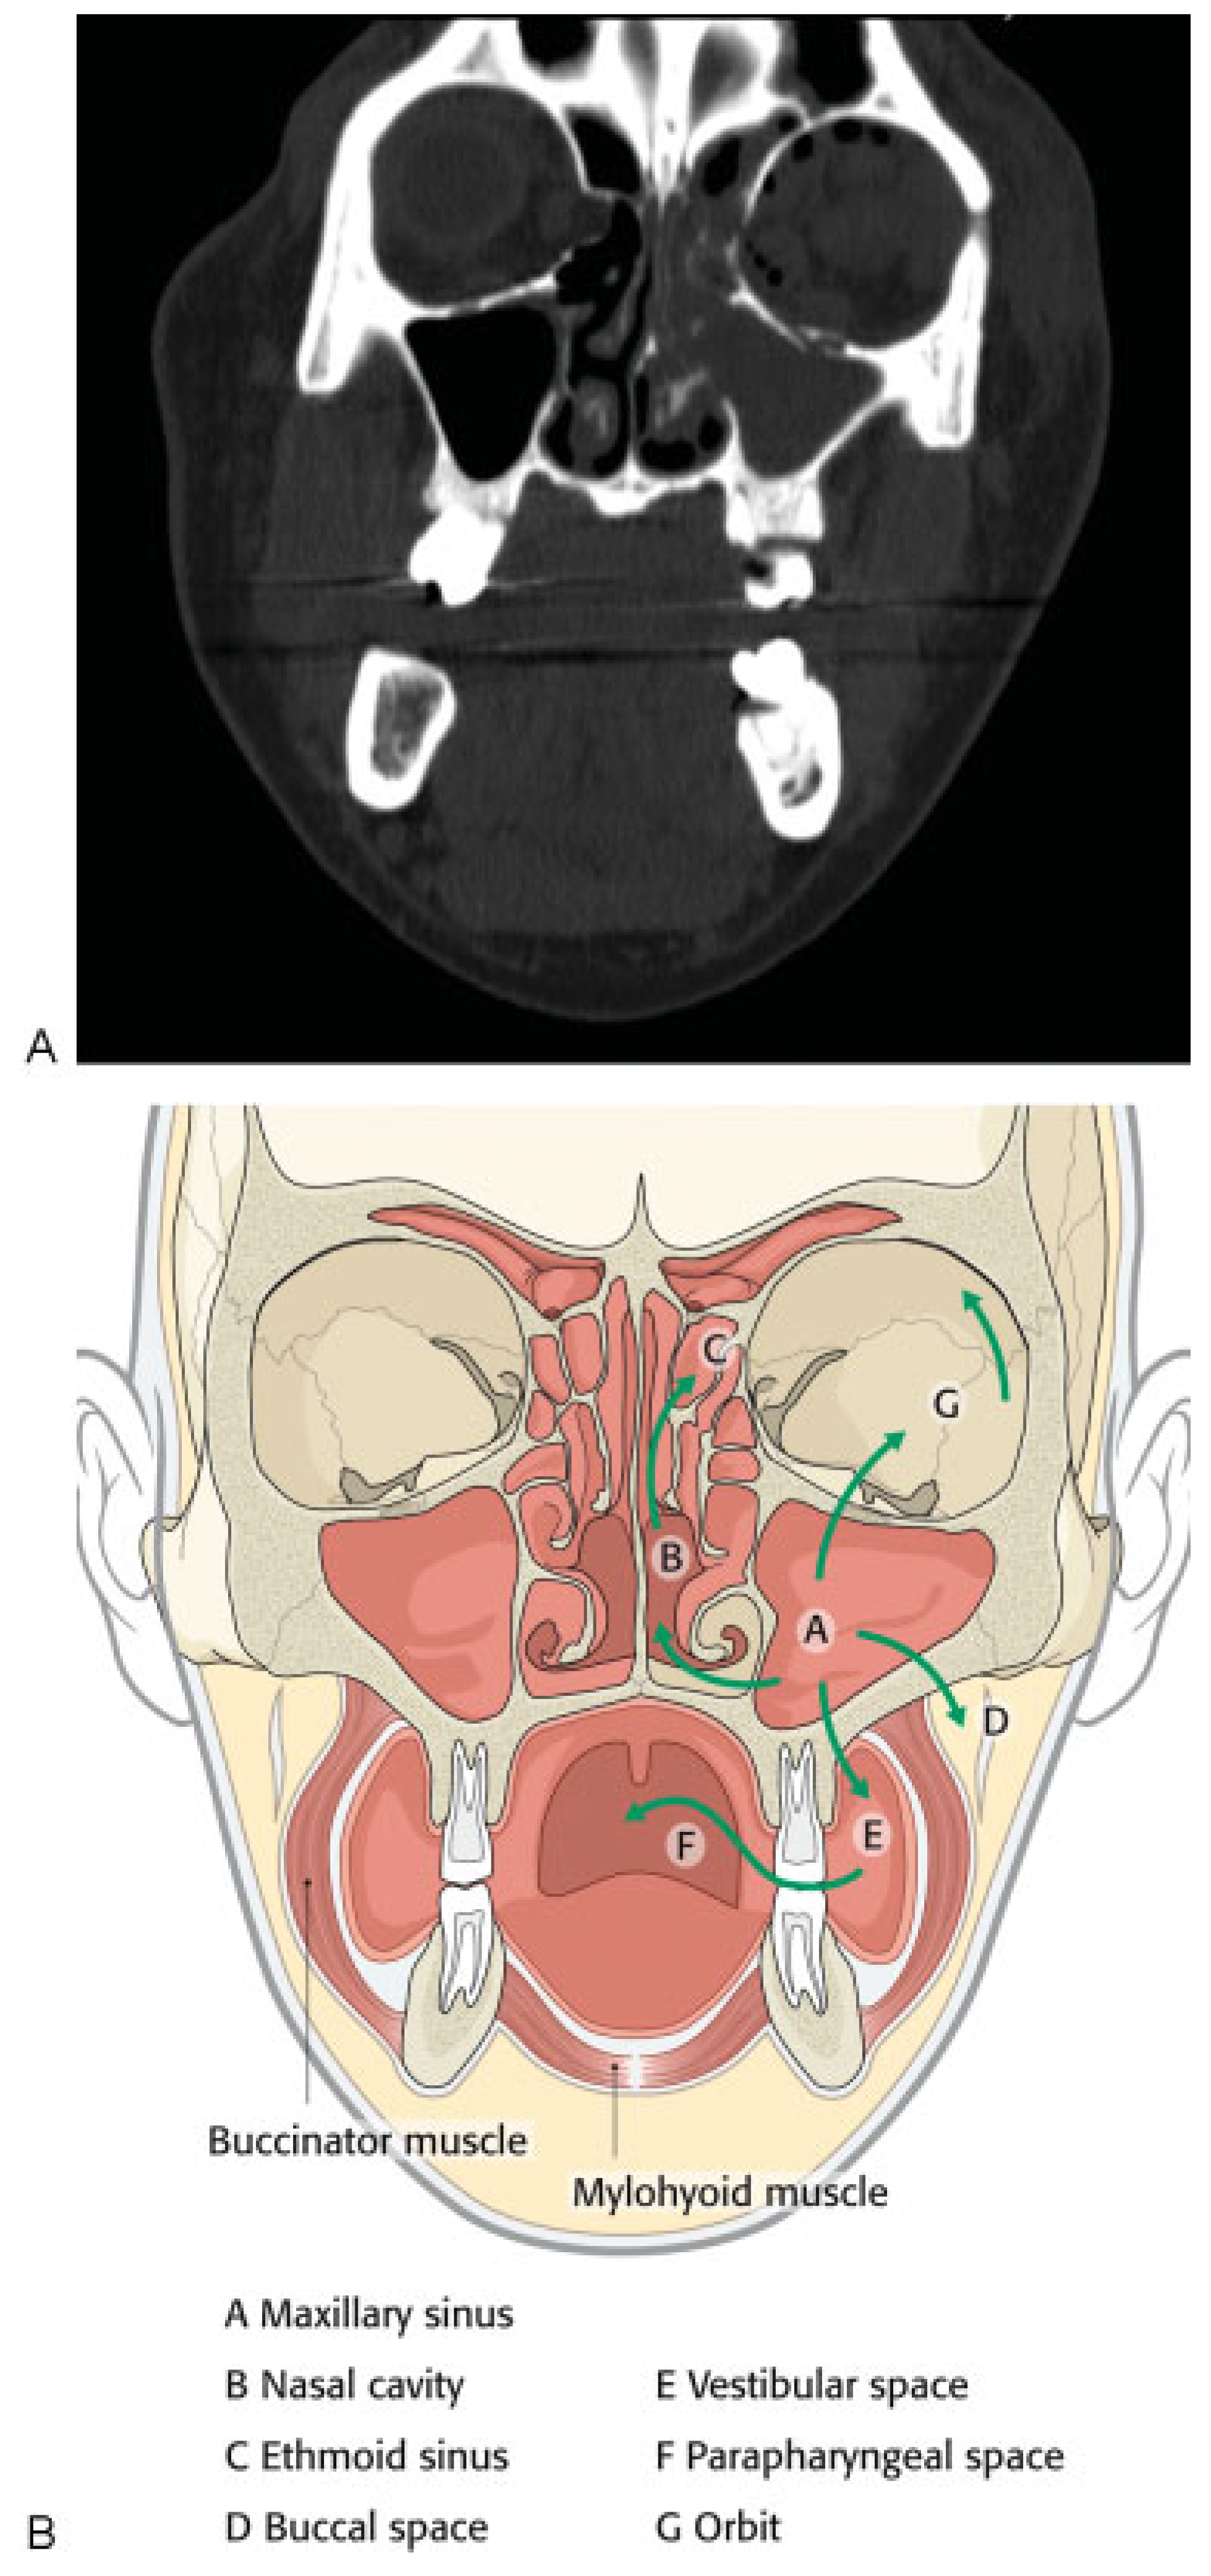

The patient was taken immediately to the operating room due to her worsening clinical presentation and the authors’ suspicion for necrotizing soft tissue infection. Incision and drainage and debridement of the necrotic tissue were performed on the left periorbital, zygomatic, and temporal regions (►Figure 3A–D). Copious purulent drainage was obtained which was submitted for Gram stain and cultures. Irrigation of the wound was then performed until no further murky fluid was appreciated with approximately 5 L of 0.9% normal saline. The wound was then packed in a standard wetto-dry fashion. The patient was placed on vancomycin, piper-acillin/tazobactam, and metronidazole and transferred to the intensive care unit (ICU) where she remained intubated and sedated. In the ICU, she was supported medically, including optimization of her blood glucose. Overnight, the patient remained tachycardic and febrile with a maximum temperature of 103°F (39.4 °C). At that time, a maxillofacial CT with contrast was obtained, which revealed left periorbital, orbital, and buccal inflammatory changes. Proptosis, lateral and downward displacement of the globe, and homogeneous opacification of the frontal, ethmoid, and maxillary sinuses were appreciated on the left side. The right ethmoid sinus was partially opacified, which justified the inflammatory changes in the right orbit. Additionally, a large fluid loculation of the left lateral pharyngeal space was present (►Figure 4). The intraoral examination revealed a large localized swelling of the left oropharynx and nasopharynx, with deviation of the palatal uvula from the midline. Ophthalmology was reconsulted. On postoperative day 2, the patient was taken back to the operating room for incision and drainage of the left maxillary sinus and left lateral pharyngeal space and washout of existing wound. An intraoral incision was made on the left posterior oropharynx and blunt dissection was performed to enter the left lateral pharyngeal space where approximately 15 mL of purulence was obtained and samples were sent for cultures and sensitivities. Three nonrestorable, grossly carious left maxillary posterior teeth were then extracted to negate any possible source of odontogenic infection; however, no purulence or periapical involvement of the teeth was evident upon extraction. This made an odontogenic cause of the infection unlikely. The left maxillary sinus was entered via a standard Caldwell-Luc approach to drain the fluid collection appreciated on CT and an additional 5 to 10 mL of purulence was obtained. After copious irrigation of the sites, two ½ inch Penrose drains were placed, one in the left maxillary sinus and the other in the left lateral pharyngeal space. The drains were then secured to the oral mucosa with sutures. Washout and redressing of the left periorbital wound was then performed and the patient returned to the ICU intubated. Laboratory values showed white blood cell count of 15.9 g/dL, hemoglobin of 12 g/dL, hematocrit of 36.4%, and platelet count of 226,000/µL. Chemistry showed sodium level of 134 mmol/L, potassium level of 3.5 mmol/L, chloride level of 97 mmol/L, bicarbonate level of 27 mmol/L, blood urea nitrogen level of 6 mg/dL, creatinine level of 0.7 mg/dL, and glucose level of 375 mg/dL. Hemoglobin A1C was 12.8 and C-reactive protein was 34.2 mg/dL. The patient’s previously recorded hemoglobin A1C was 13.0 recorded 26 months earlier at the medicine clinic showing long-term poor diabetic control. Over the next few days, the patient clinically improved and her vital signs stabilized with the exception of a persistent elevated temperature of 101°F. Cultures came back as group C β hemolytic Steptococcus and Proteus mirabilis. After consultation with the infectious disease service, the antibiotics were narrowed to ampicillin/sulbactam and clindamycin. A repeat CT scan was obtained on hospital day 5 and a loculation was noted at the superior and lateral aspect of the left orbit, suggestive of subperiosteal abscess (►Figure 5A,B). Ophthalmology service recommended no intervention for the left orbital subperiosteal abscess. However, as the patient was still having low-grade temperature of 101°F (38.3 °C), the authors took the patient back to the operating room for incision and drainage of this area. We approached the superior-lateral orbit via an existing incision, and approximately 5 mL of purulence was obtained. Postoperatively, the patient improved clinically, and became afebrile. The intraoral drains were removed, and after cons ultation with the wound nurse, the wet-to-dry dressing of the skin was changed to petroleum-impregnated gauze. Despite our objection, the patient remained intubated for a prolonged period due to the discomfort of the ICU team in extubating the patient. The patient was extubated on hospital day 12. On the day of discharge, examination revealed significant decrease in left periorbital swelling, decrease proptosis, and increase extraocular movement in all directions; however, she continued to have 20/400 vision in the left eye and diplopia. Due to the defect in the left upper and lower eyelids, a home care nurse was assigned for daily dressing changes. Intraoral examination demonstrated resolution of swelling of the oropharynx. A maxillofacial CT scan revealed resolution of the original fluid loculations and a patent airway. Throughout the postoperative hospital stay, the patient’s glucose level and blood pressure were controlled. The patient was discharged on hospital day 13 with oral antibiotics, amoxicillin/clavulanic acid, and clindamycin, as well as her home antihypertensive and diabetic medications. The patient was closely followed up and her condition continued to improve. At 4 months follow-up, the patient presented with resolution of facial swelling; had proptosis and eyelid ptosis, normal extraocular movements; and her baseline visual acuity of her left eye remained 20/400. The patient was seen 1 year postoperatively and had continued resolution of her wounds with appropriate wound closure; however, she had continued strabismus, ptosis of the upper and lower lid secondary to scar contraction, as well as left V2 paresthesia (►Figure 6A,B). The orbital wound continued to heal via secondary intention with anticipated reconstruction and scar revision in the near future.

Figure 5. Axial and coronal computed tomographic scan illustrating a sub-periosteal abscess at the lateral (A) and superior (B) aspect of the left orbit. Arrow on A shows abscess on lateral orbit and arrow on B shows abscess on inferolateral orbit.